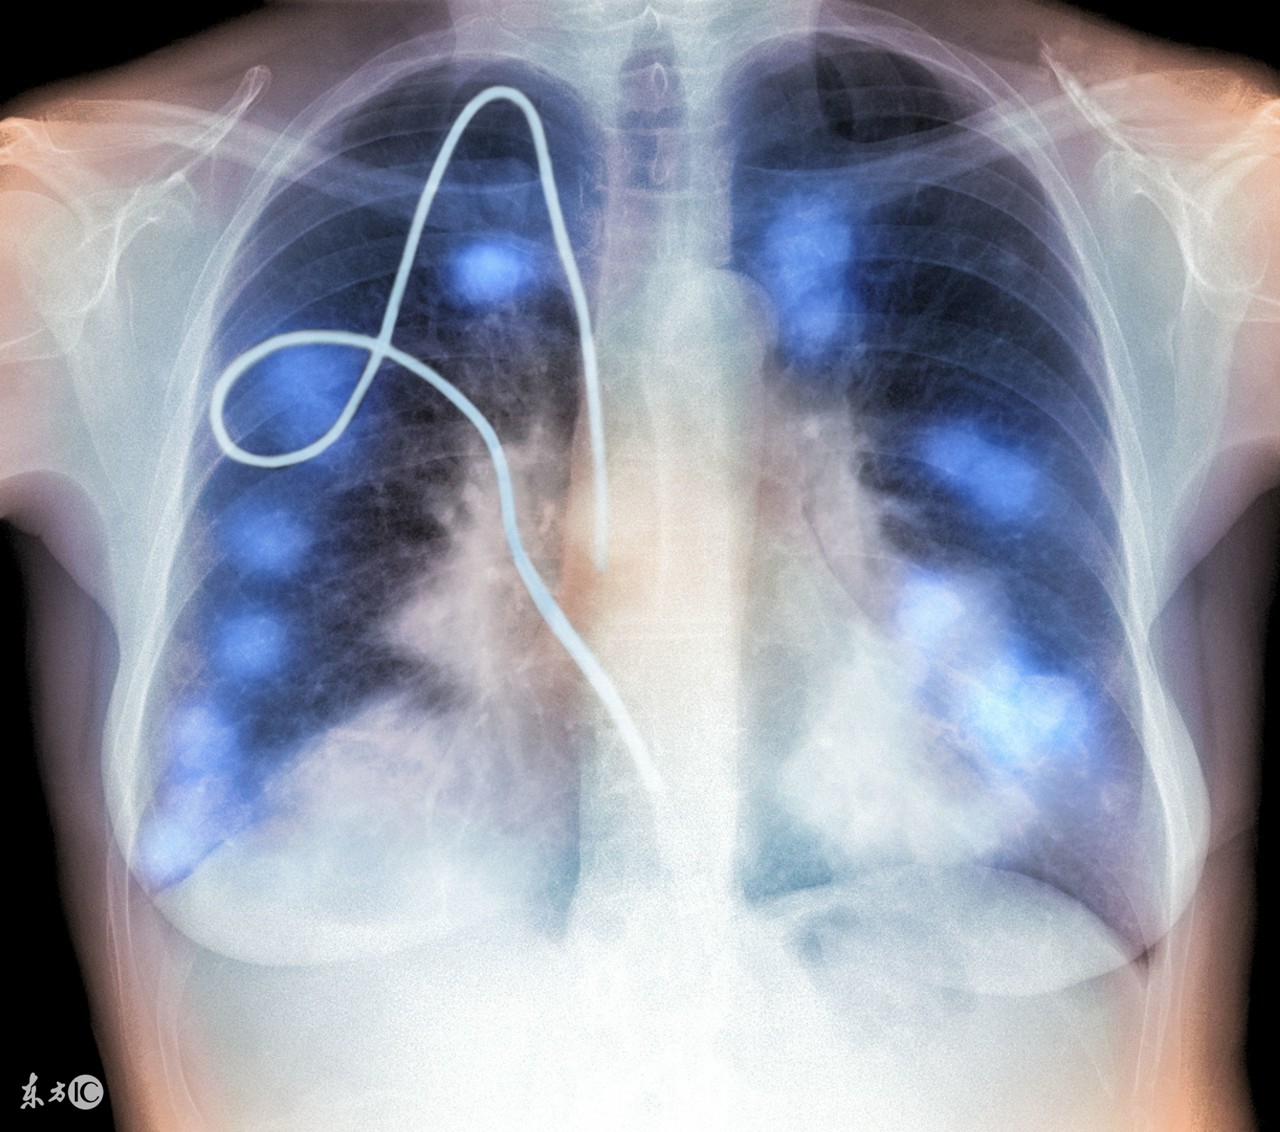

肺假性肿瘤可以通过X线检查、CT检查、纤维支气管镜三种方式检查出,所以并不难诊断。因此诊断出肺假性肿瘤的几率越来越高,对患者查明病情、对症治疗、消除患者顾虑有很大的帮助